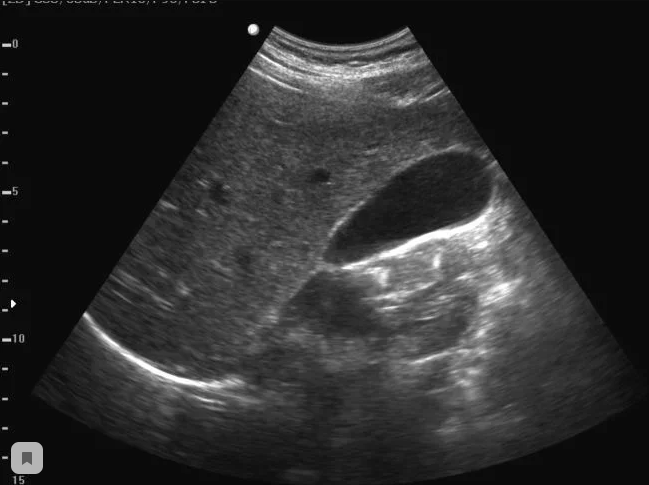

Врач назначил мужу УЗИ, которое показало, что у него в желчном пузыре много билирубиновых камней. Как объяснил врач, такие камни не рассасываются от простых лекарств, и нужно в любом случае оперироваться и удалять желчный.

Продолжительность лечения по болотовской методике – 2-4 недели. После 2 недель лечения муж почувствовал себя значительно лучше и вновь прошел УЗИ. Результаты нас очень обрадовали. Камни стали мельче и их стало меньше. Видимо, некоторые из них за это время вышли естественным путем. И в целом он стал чувствовать себя лучше. Пропала изжога и тошнота, боли практически исчезли. Что меня удивило, так это то, что Славик сам предложил продолжить лечение! Сам напоминал мне о том, что пора бы уже и дозу принять).

После месяца такого лечения и повторного УЗИ камней в желчном пузыре мужа уже не обнаружили. Он полностью излечился от желчнокаменной болезни. Но сказал мне, что периодически будет пить желчь для профилактики.